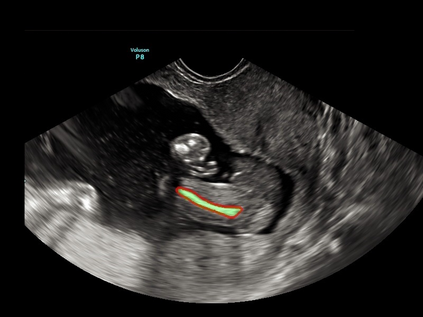

In this paper, we propose an end-to-end multi-task neural network called FetalNet with an attention mechanism and stacked module for spatio-temporal fetal ultrasound scan video analysis. Fetal biometric measurement is a standard examination during pregnancy used for the fetus growth monitoring and estimation of gestational age and fetal weight. The main goal in fetal ultrasound scan video analysis is to find proper standard planes to measure the fetal head, abdomen and femur. Due to natural high speckle noise and shadows in ultrasound data, medical expertise and sonographic experience are required to find the appropriate acquisition plane and perform accurate measurements of the fetus. In addition, existing computer-aided methods for fetal US biometric measurement address only one single image frame without considering temporal features. To address these shortcomings, we propose an end-to-end multi-task neural network for spatio-temporal ultrasound scan video analysis to simultaneously localize, classify and measure the fetal body parts. We propose a new encoder-decoder segmentation architecture that incorporates a classification branch. Additionally, we employ an attention mechanism with a stacked module to learn salient maps to suppress irrelevant US regions and efficient scan plane localization. We trained on the fetal ultrasound video comes from routine examinations of 700 different patients. Our method called FetalNet outperforms existing state-of-the-art methods in both classification and segmentation in fetal ultrasound video recordings.